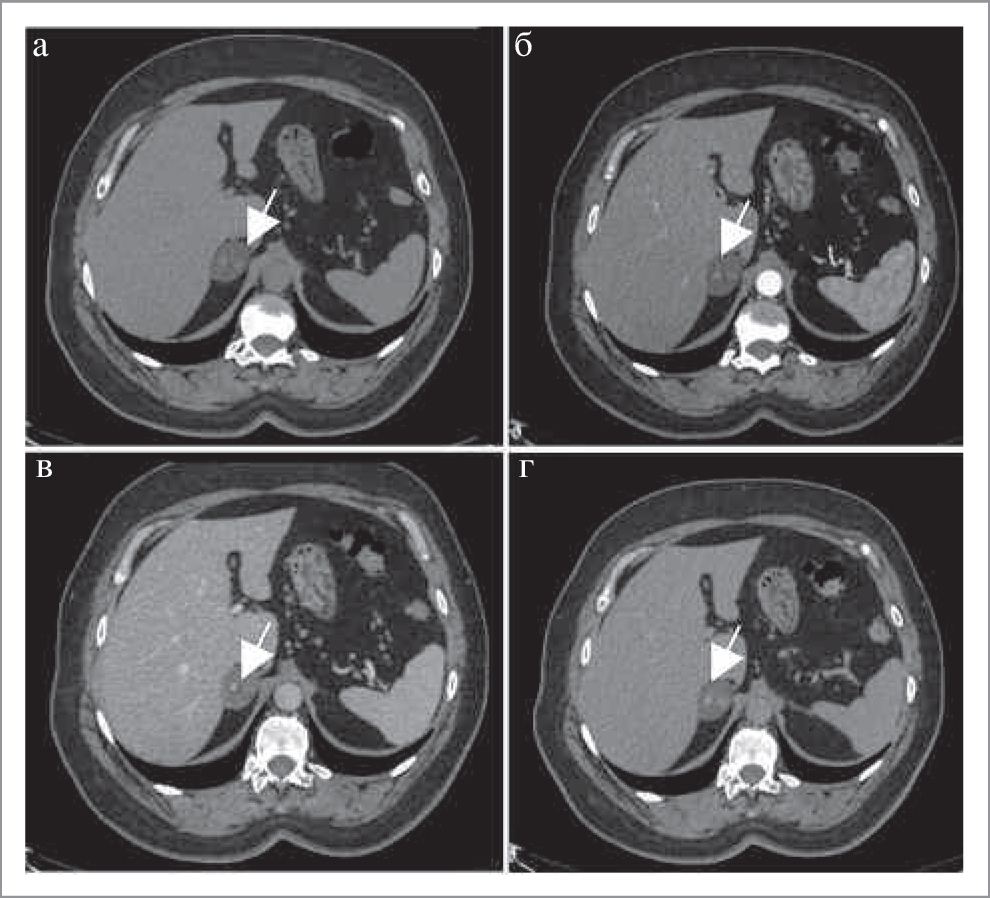

КТ-картина феохромоцитом имеет различные признаки. Размер может варьировать от 1,2 до 15 см, в среднем около 5 см. Небольшие образования чаще однородны, в то время как более крупные часто неоднородны с участками жидкостной плотности (зонами некроза), зонами кровоизлияний, внутренними перегородками, а также обызвествлениями. Большинство опухолей интенсивно накапливает контрастный препарат в АФ с последующим умеренным его вымыванием к ОФ. Контуры образования, как правило, четкие, ровные за счет наличия капсулы (рис. 6). В редких случаях феохромоцитомы могут иметь включения макроструктурного жира, что также характерно и для миелолипом [16].

Рис. 6. МСКТ, аксиальная проекция: а – НФ; б – АФ; в – ВФ; г – ОФ. Параганглиома (стрелка).

Озлокачествление опухоли наблюдается в 11% случаев у спорадических феохромоцитом и в 35% случаев наследственных феохромоцитом [19]. Выявление метастазов (чаще в костях, лимфатических узлах, легких и печени) подтверждает озлокачествление образования. Следует отметить, что, несмотря на то, что выраженное вымывание контрастного препарата для феохромоцитом нехарактерно, в редких случаях они могут иметь характеристики вымывания, аналогичные аденомам (APW более 60% и RPW более 40%), что затрудняет установку диагноза [16].